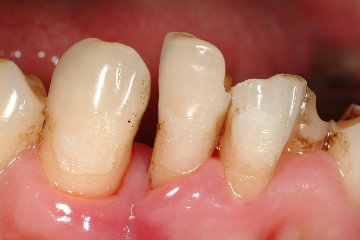

立即植牙-下顎側門齒嚴重牙周病

圖一 |